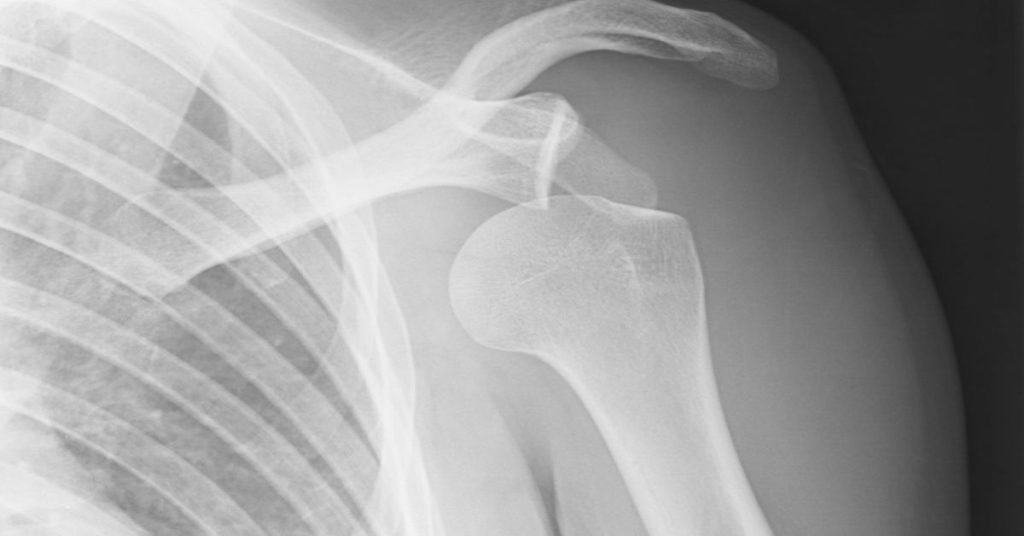

Tanı sürecinde doktor önce hastayı muayene eder. Ardından görüntüleme yöntemleri kullanılır. Röntgen veya gelişmiş tetkikler eklemdeki hasarı gösterir. Tedavi planı hastanın yaşına ve yaralanmanın şiddetine göre belirlenir. Çoğu vakada eklem yerine yerleştirilir. Sonrasında askı kullanımı ve istirahat önerilir. Kontrollü egzersizler de tedaviye eklenir. Bu egzersizler kasları güçlendirir. Düzenli kontroller iyileşmenin güvenli ilerlemesini sağlar.

Omuz çıkığı tedavisinde temel amaç, eklemi güvenli şekilde yerine yerleştirmek ve tekrar çıkık oluşmasını önlemektir. Yaralanma sonrası hastada ağrı ve hareket kısıtlılığı görülür. Bu nedenle erken müdahale büyük önem taşır. Hastaneye başvurulduğunda önce muayene yapılır ve görüntüleme yöntemleri ile hasar değerlendirilir. Kemik, bağ ve kas yapılarında ek bir yaralanma olup olmadığı kontrol edilir. Ardından kişiye uygun tedavi yöntemi planlanır ve süreç dikkatle takip edilir.